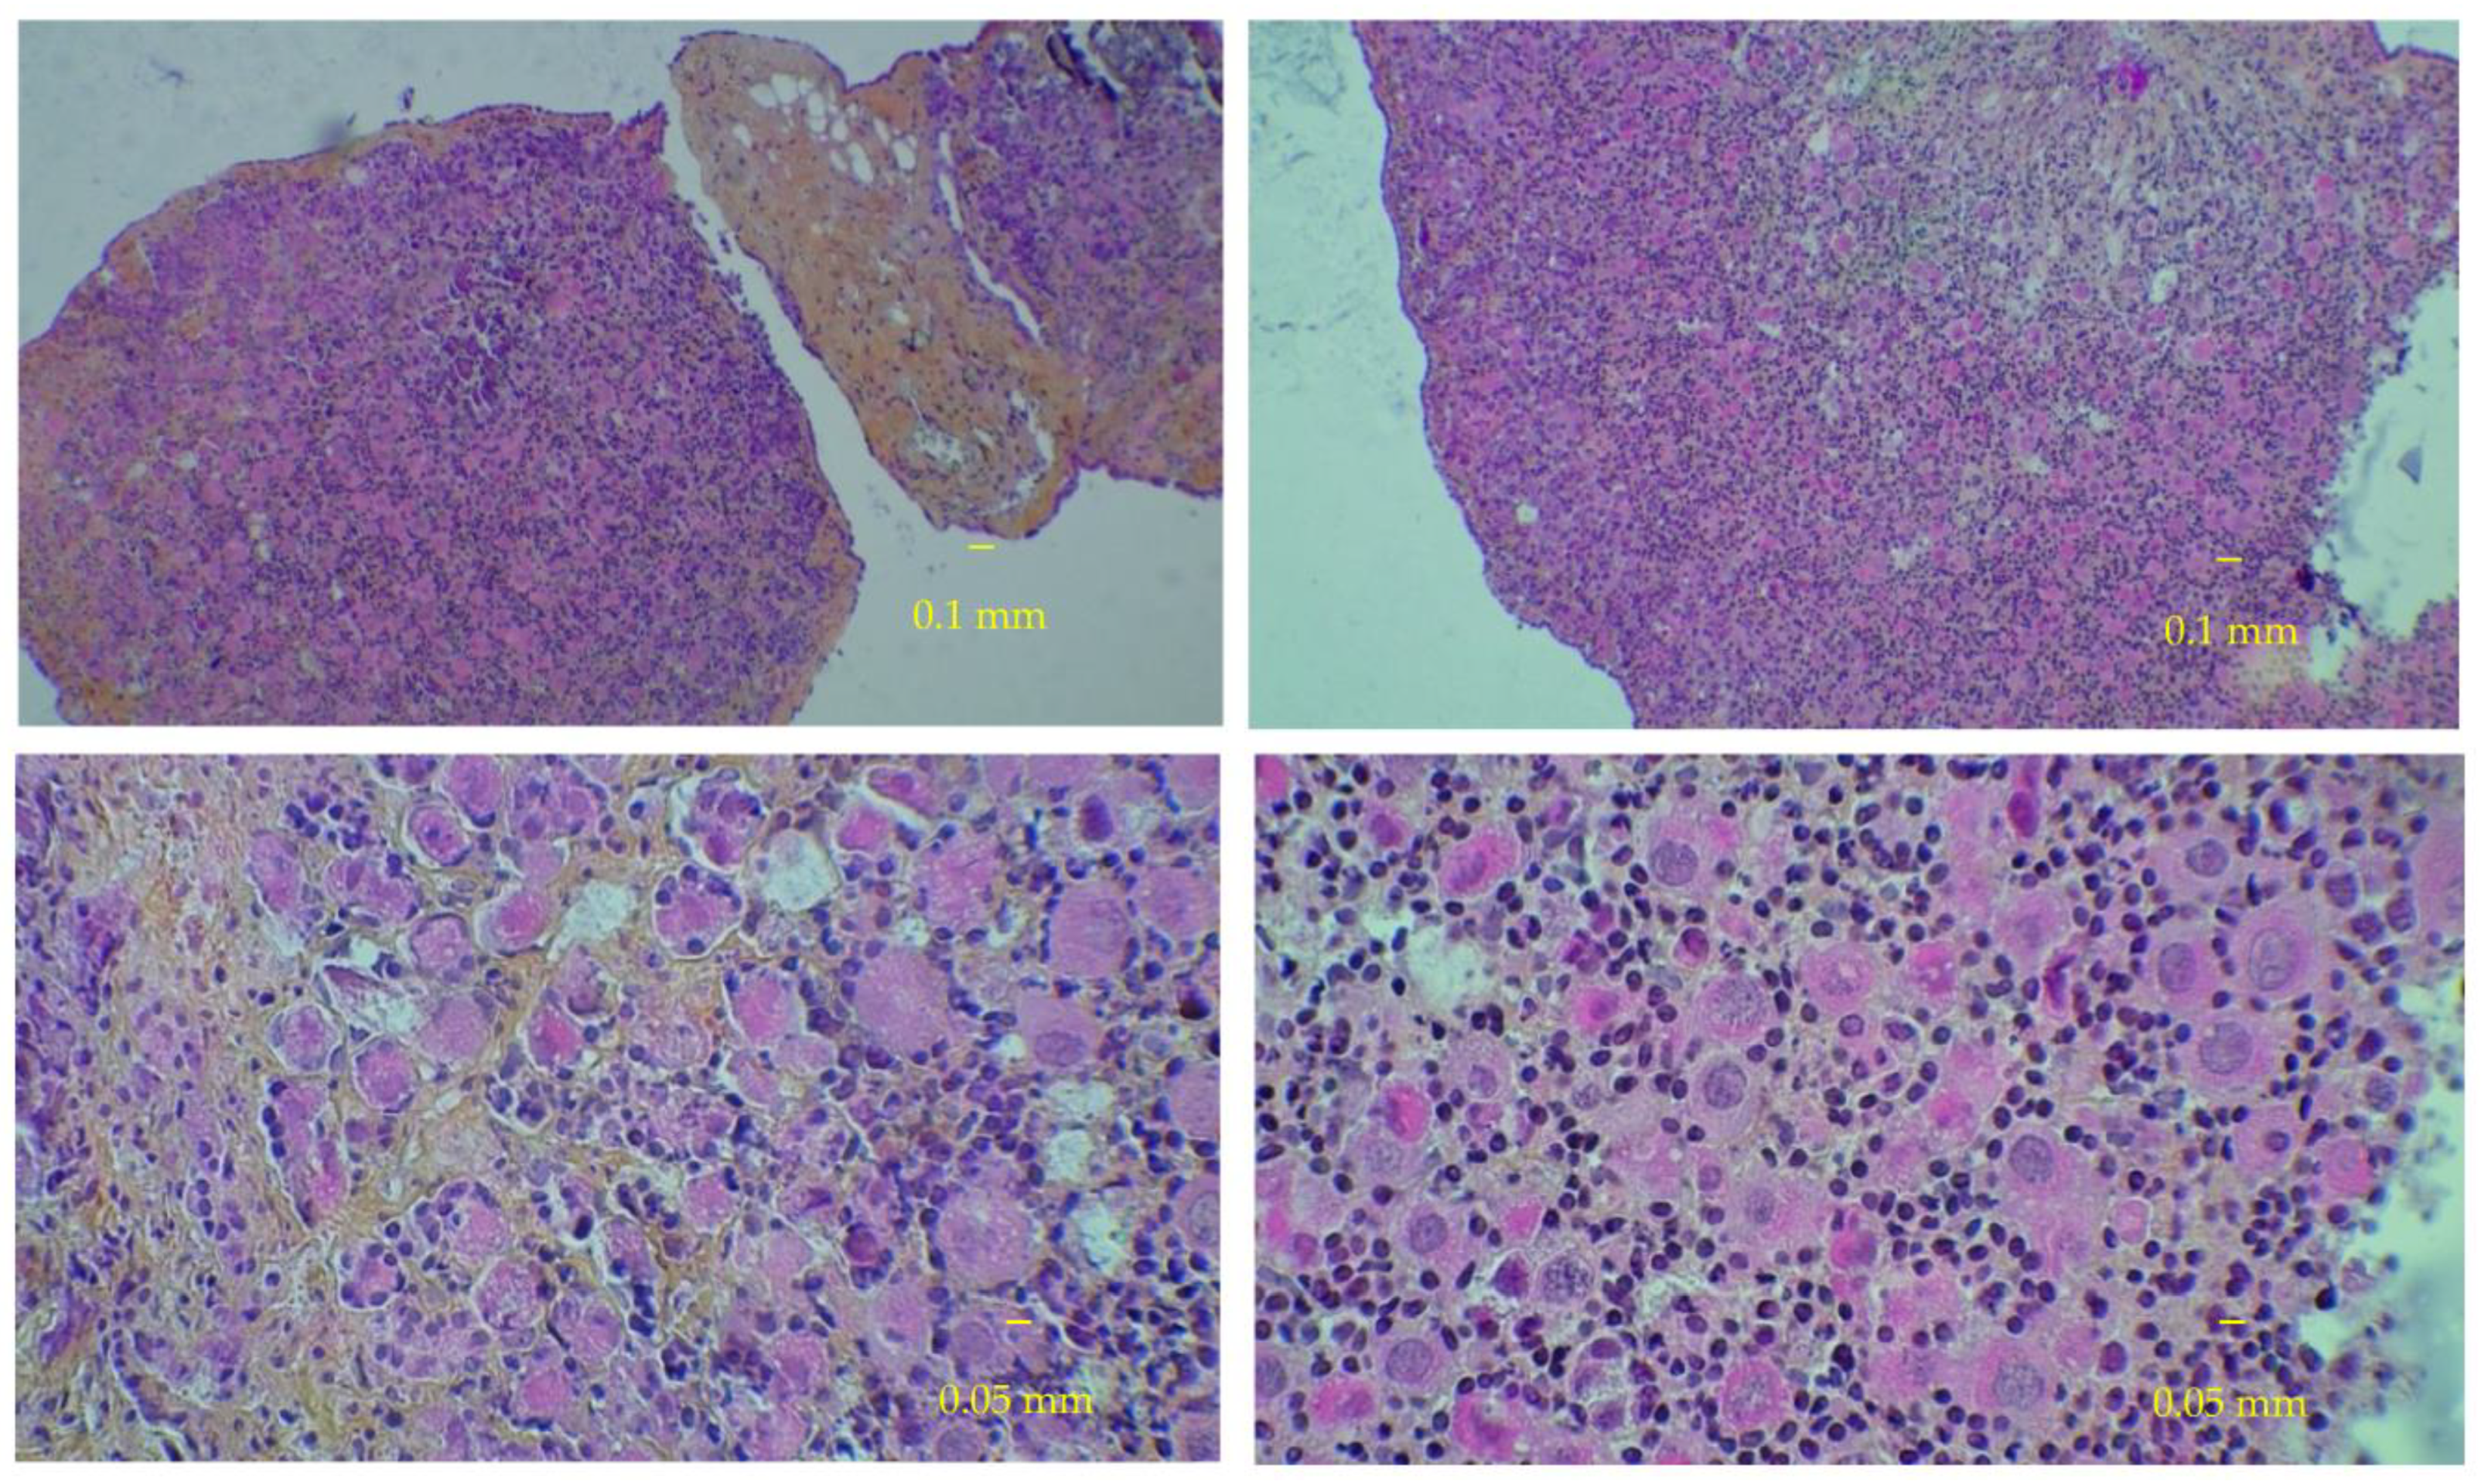

2.4. Histological Analyses

3.3. Immunostaining for Cell Apoptosis